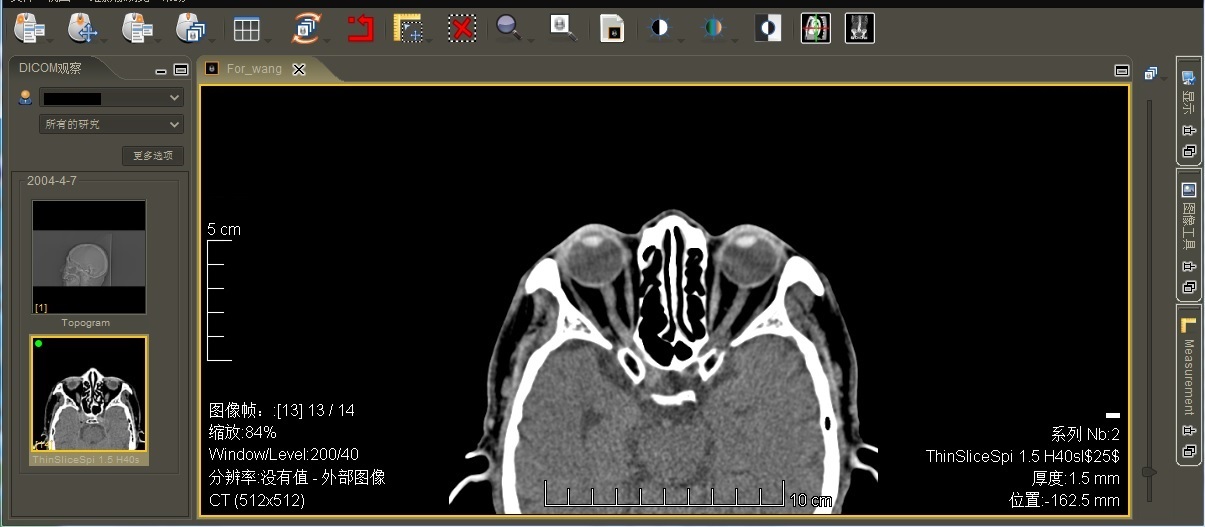

4.影像处理 支持DICOM3.0标准,可进行调节窗宽窗位、缩放、测距、旋转、明度调整,图像漫游等DICOM图像处理功能。